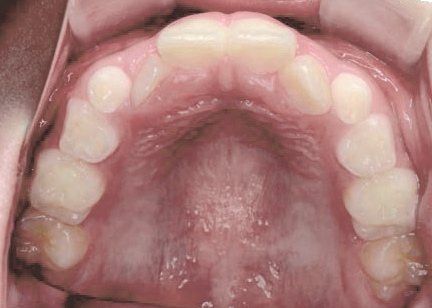

出っ歯

あごや骨格を正しく成長させる矯正治療

Aさん (矯正開始時:8歳)

Before

After

鼻がつまりやすく、口呼吸をしているために上あごが狭い状態でした。また上の前歯がかなり前へ傾いているため、お口をきちんと閉じていることができません。さらに、下の前歯もでこぼこしていました。

治療を終えて

装置によって上あごを拡大し、下あごを少し前へ成長させたことで、永久歯がきれいに並ぶスペースを確保しました。また、お口の機能が向上したことから鼻がよく通るようになり、口呼吸も改善され口も閉じやすくなったので顔の表情もよくなりました。

主訴・治療内容 下あごが後ろに下がり、出っ歯のようになっていることを心配して、無料相談に来院されました。

治療期間 2年半

費用 462,000円(税込)